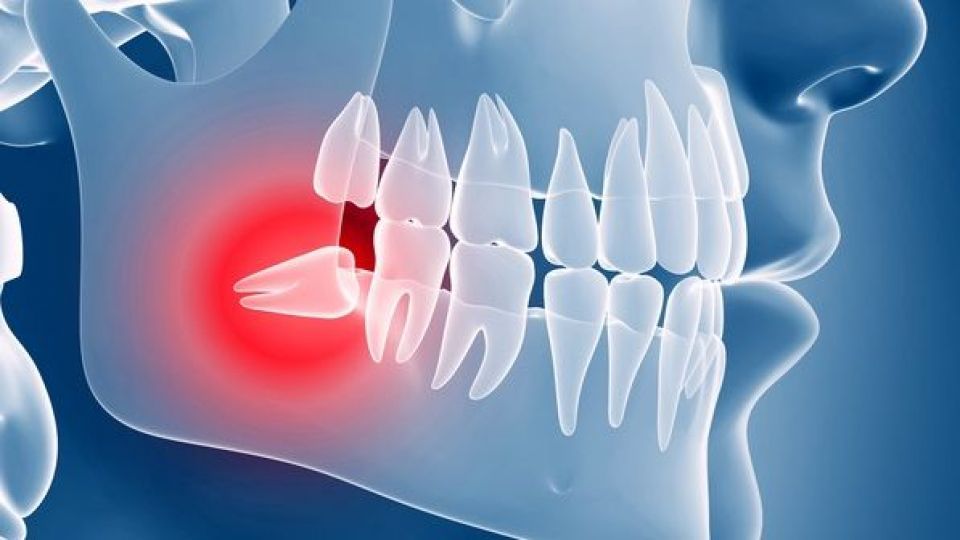

این جراح لثه و ایمپلنت با بیان اینکه گاهی به دلیل کج بودن رویش دندان نیز لازم است این دندان کشیده شود، افزود: زیرا چرخش کاملی در آن صورت نمیگیرد و دندان کج میماند و البته در این حالت کشیده شدن آن لازم است. تنها در صورتی که وجود دندان منجر به ناهنجاریها شود، توصیه به کشیده شدن یا جراحی آن میشود.